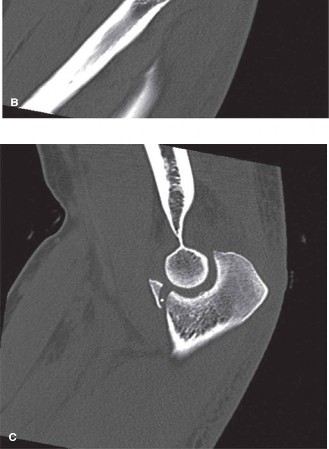

التصوير المقطعي المحوسب (CT Scan):

-

ضروري للغاية.

يوفر التصوير المقطعي عالي الدقة مع إعادة البناء ثلاثي الأبعاد معلومات لا تقدر بثمن حول:

- شكل كسر الناتئ الإكليلي: حجم الكسر، تفتته، إزاحته، ومدى تأثيره على الحديبة السامية (التي تُعد نقطة ربط حاسمة للرباط الجانبي الإنسي).

- نمط كسر رأس الكعبرة: عدد الشظايا، إزاحتها، ووجود أي تدرج في السطح المفصلي.

- سلامة عظمي العضد والزند: استبعاد أي كسور مصاحبة.

- تطابق الرد: تأكيد الرد المركزي للمفصل إذا تم إجراؤه قبل التصوير المقطعي.

صورة بالأشعة المقطعية تظهر إصابة ثلاثي الكوع الرهيب، مع كسور في رأس الكعبرة والناتئ الإكليلي وخلع مصاحب. تُعد الأشعة المقطعية الشاملة ضرورية لتقييم الكسور بدقة.